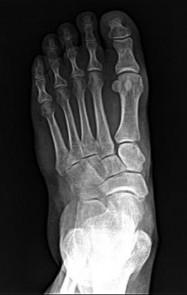

Question 9:

A 24-year-old professional football player sustains a high-energy axial load injury to a plantarflexed foot. Radiographs demonstrate widening of the midfoot spaces. The critical interosseous Lisfranc ligament connects which of the following two osseous structures?

Correct Answer: Medial cuneiform to the base of the second metatarsal

Explanation:

The Lisfranc ligament is a strong interosseous ligament critical for the stability of the tarsometatarsal joint complex. It originates from the lateral aspect of the medial cuneiform and inserts onto the medial aspect of the base of the second metatarsal. There is no direct ligamentous connection between the bases of the first and second metatarsals, making the Lisfranc ligament the primary restraint to lateral displacement of the lesser metatarsals.